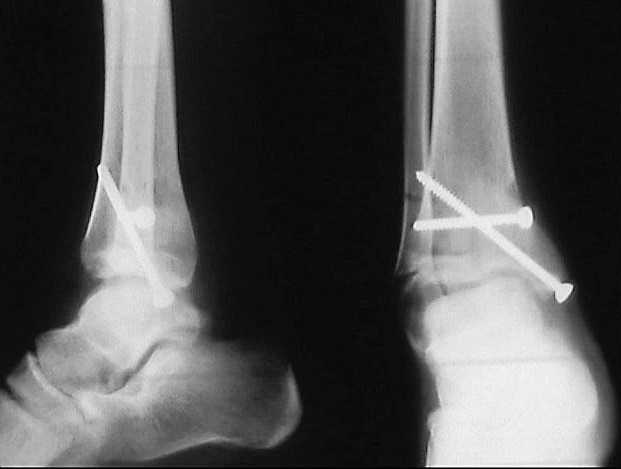

Скорее это перелом пилона 43В

Оперировать. Остеотомия, исправлять ось. Вопрос чем фиксировать? Зависит от того, чем владеете, что у вас есть в отделении, что может себе позволить пациент.

Я бы фиксировал пластинами LCP: 1\3 трубки на м\б и метафизарную 3,5/4,5/5,0 или DMT на б\б...

Но можно гвоздем, можно и аппаратом...

Согласен, тут деформация меньше, но все-таки заметная, почти 20 градусов. Я бы устранял ее как на приложенной картинке.

При таком варианте с аппаратом все легко и просто. С пластиной - должны быть трудности. Может быть, следовало бы планировать коррекцию как-то иначе? Как?